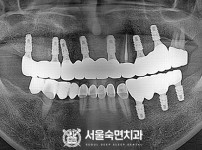

임플란트-전후사진3

임플란트-전후사진4